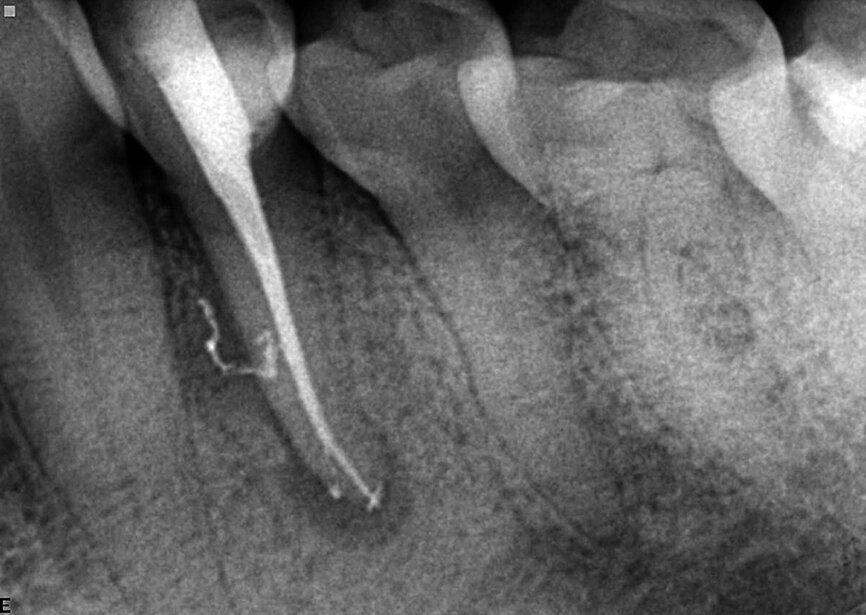

Fig. 3: A necrotic/infected case: Lower premolar of the patient complaining of dull and pulsating pain. The infection was not limited to the apical part, but was also located in the lateral mid-root section. Postoperative X-ray shows a 3-D sealing of the apical area with its anastomosis and of the lateral and accessory canals in mid root.

Fig. 4: Complexity of the apical area manifests itself after it was treated chemically, dried, and sealed by way of the warm vertical technique.